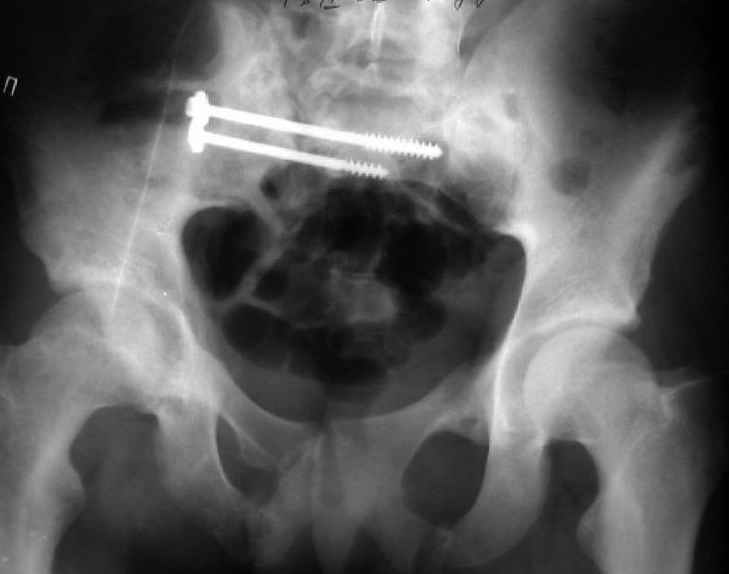

Уважаемые коллеги! Хотел-бы обсудить варианты лечения больной с застарелым переломом таза. Возраст 40 лет. Травма 11 месяцев назад. Главный травматолог Камчатского Военно-морского госпиталя Юрий Алексеевич Булахтин

У больного судя по всему вертикальная деформация таза. А каковы основные жалобы пациента и какие у него функциональные требования?

Мы, как правило, в подобных случаях проводим оперативное лечение в несколько этапов. Первым устраняем деформацию при помощи АВФ (кольцевой конструкции с фиксацией задних отделов), вторым- выполняем введение илиосакралых винтов, накостный остеосинтез передних отделов.

Для информации к размышлению о возможности исправления имеющейся деформации предлагаю похожий случай.